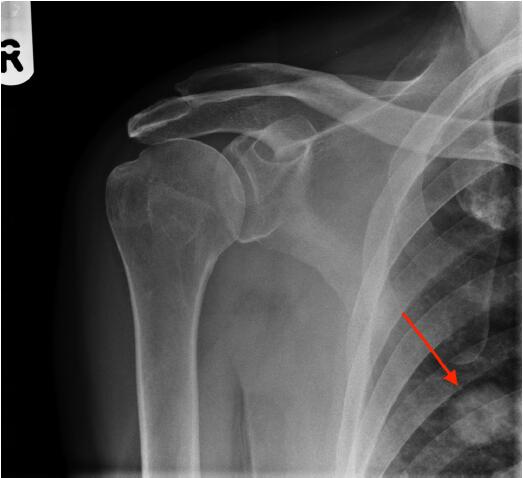

圖2肩X光片顯示一空洞性肺結(jié)節(jié),約2cm。很可能是原發(fā)性肺癌,需要轉(zhuǎn)診至肺癌多學(xué)科小組。

圖2右肩前位X光平片,紅色箭頭指示一空洞性肺結(jié)節(jié)

該例患者接受了胸部和腹部CT掃描,隨后取了活檢,證實(shí)為T(mén)2N0M0原發(fā)性肺腺癌。對(duì)給患者予以手術(shù)切除,2年隨訪時(shí)仍無(wú)病。